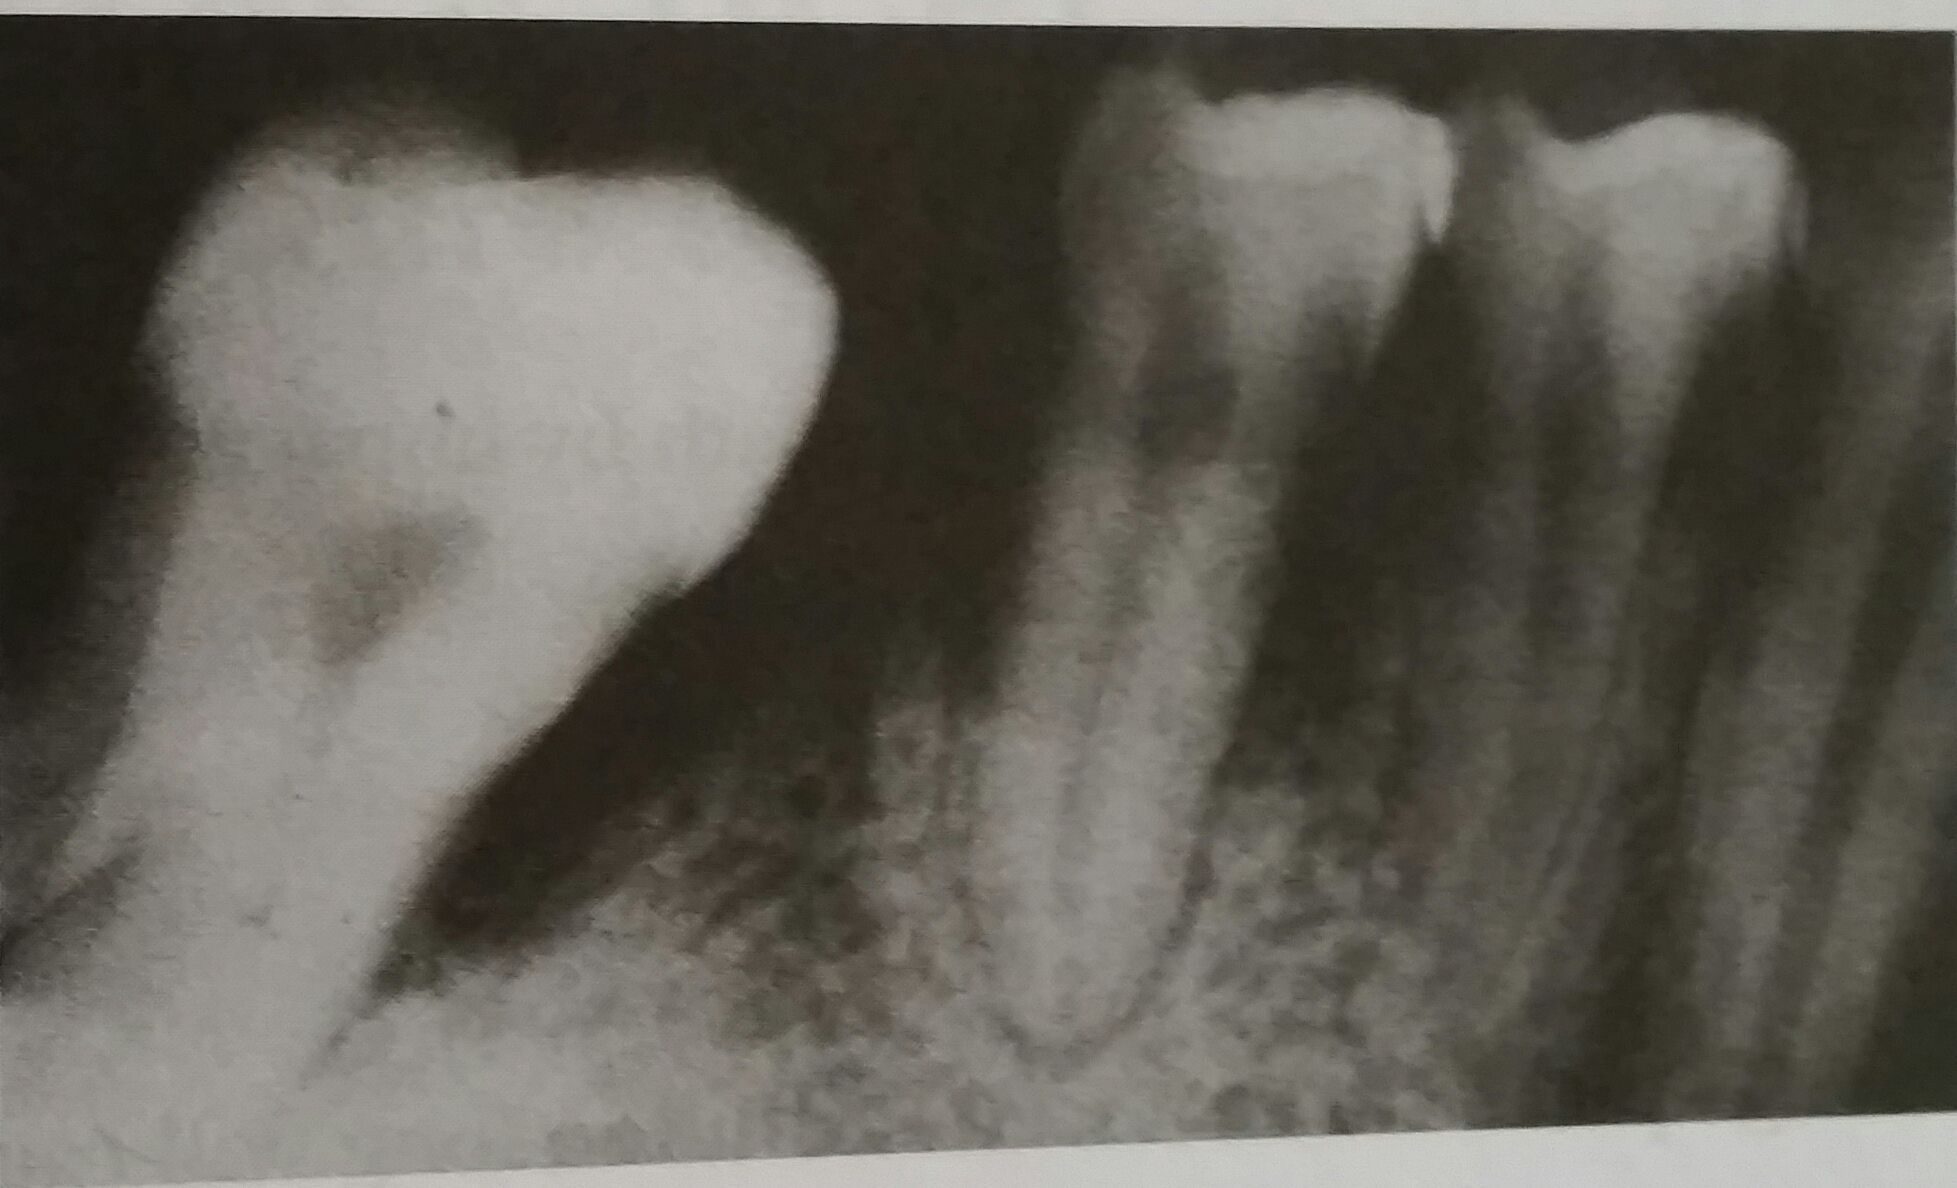

rapaque areas visible in the medial and distal roots of molars are,  | root canals with gutta percha |

what is the restoration visible in second molar is a,  | DO amalgam |

What tooth is missing,  | #30 |

the radiolucent area involving molars and premolars shows,  | severe bone loss |

this radiograph is an example of,  | bitewing |